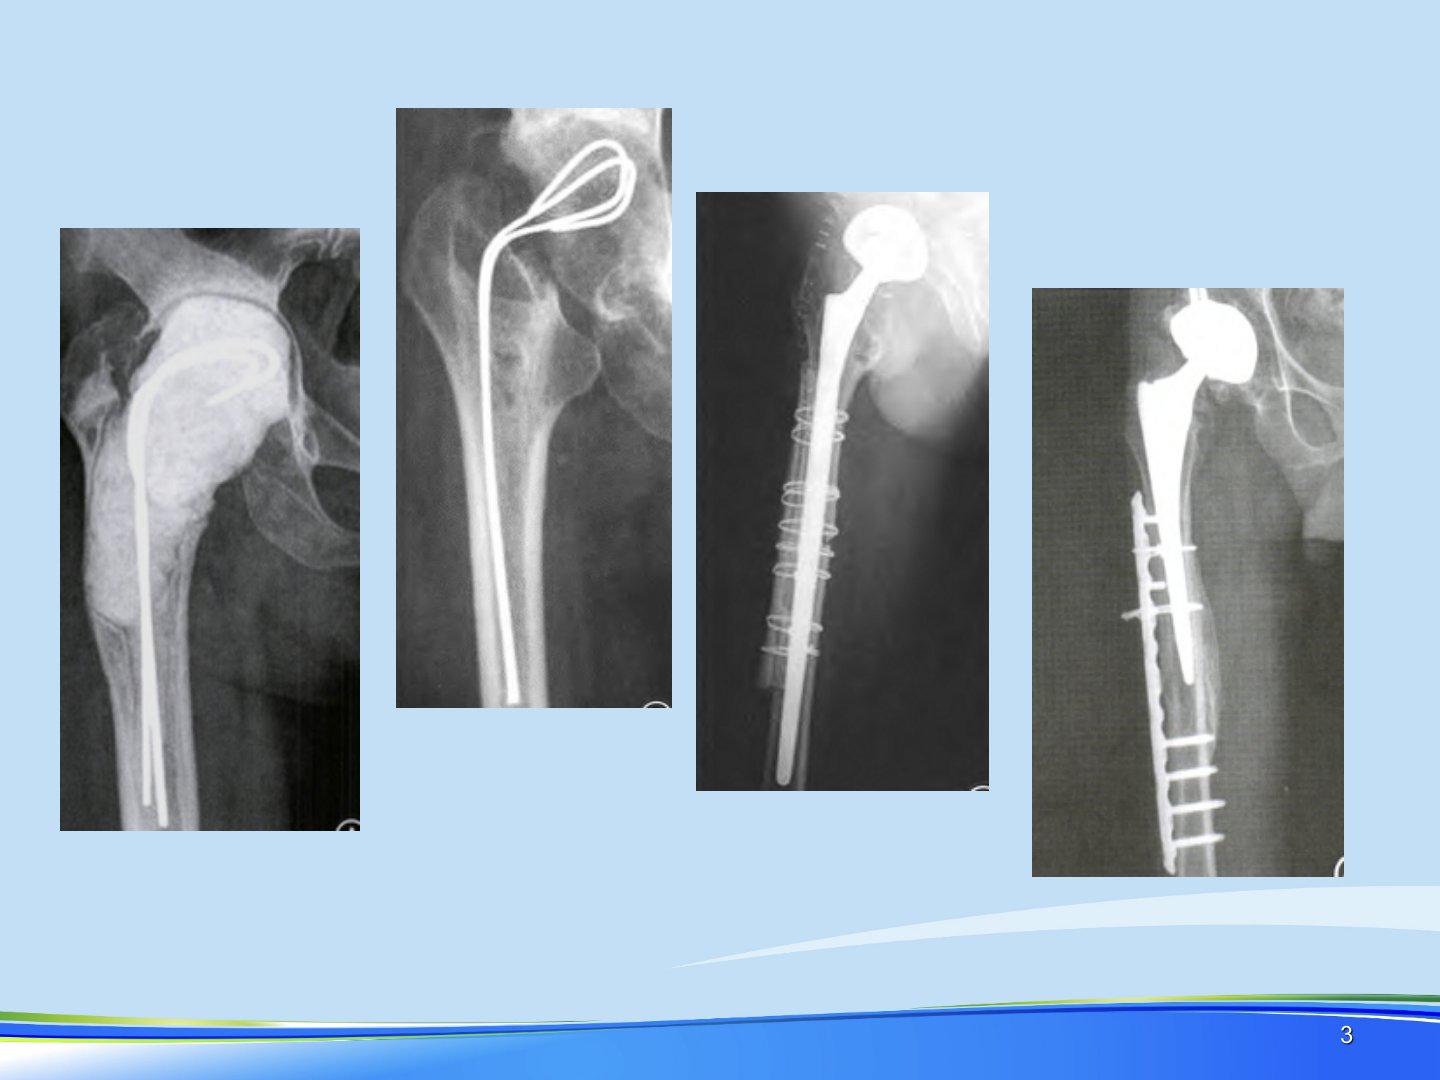

髋关节假体周围骨折的诊治摘要髋关节假体周围骨折发生率逐年上升翻修原因包括关节不稳、脱位、假体松动、感染等。其中股骨假体周围骨折危害大早期文献显示其死亡率高且存在不愈合、再骨折、再手术率高康复困难等问题。发病机制上外伤、轻微创伤是直接原因病因包括骨皮质缺损或穿孔、假体松动、骨溶解、骨质疏松等。其发病率确切统计困难文献报道总的发病率从01到18不等。分型上存在多种系统其中Vancouver分型被公认为最有助于指导治疗和预后的一种。处理方面非手术治疗适应证少仅适用于假体稳定、无移位骨折或有手术禁忌症的患者。手术治疗除无移位的、假体稳定的VancouverA型骨折可非手术治疗外如无手术禁忌症均应手术治疗。髓内固定适用于C型骨折假体翻修适用于假体松动的骨折髓外固定则包括环扎固定、钢板螺丝钉、同种异体皮质骨板等。治疗目标是骨折愈合并接近解剖力线假体稳定恢复骨折前功能能够早期活动。